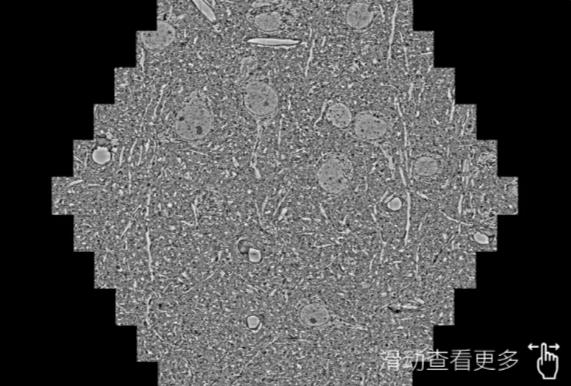

鼠脑切片。左图使用恩施蔡司恩施扫描电镜MultiSEM706对165μmx143pm面积区域成像,耗时仅需1.5秒。右图为鼠脑切片中30μm区域放大效果。样品由芝加哥大学B.Kasthuri提供。

使用蔡司高速恩施扫描电镜MultiSEM对1mm²人脑皮层组织进行高分辨成像,并对其中的各种细胞结构进行三维重构分析。左图展示了2x3mm²组织平面中锥体神经元的三维重构效果。右图显示了局部体积神经元三维重构。图像由哈佛大学chtman实验室提供,渲染图由D. Berger 制作。